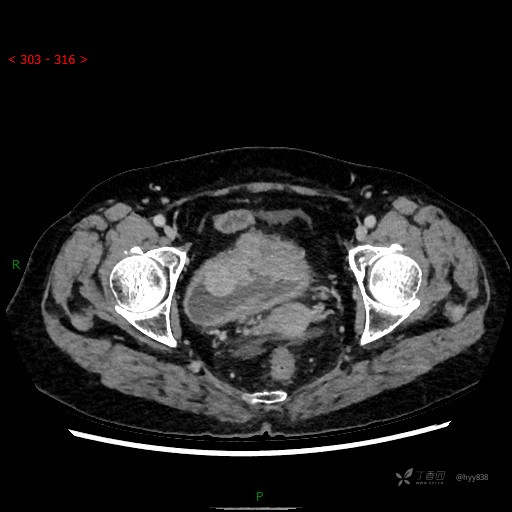

膀胱少见肿瘤,欢迎挑战---结果公布~

华夏览雄 达人已点赞患者性别:女

患者年龄:73岁

主诉:肉眼血尿3周

简要病史:患者诉3周前无明显诱因开始出现肉眼血尿,发作时尿液呈鲜红色,为全程血尿,无明显血凝块;伴小腹胀痛,无尿频、尿急、尿痛;无寒战、发热;无恶心、呕吐,就诊于当地医院行输液治疗后,出现不规则血凝块,进一步完善相关检查提示膀胱占位,活检提示膀胱炎性改变,现患者为进一步治疗,遂来我院,门诊以“膀胱肿物”为主诉入院。 起病以来,患者精神、饮食、睡眠稍差,大便如常,小便如上述,近期体力、重无明显变化

辅助检查:CT

临床诊断:膀胱肿瘤

膀胱CT平扫(2022.10.20)

增强(2022.11.1)